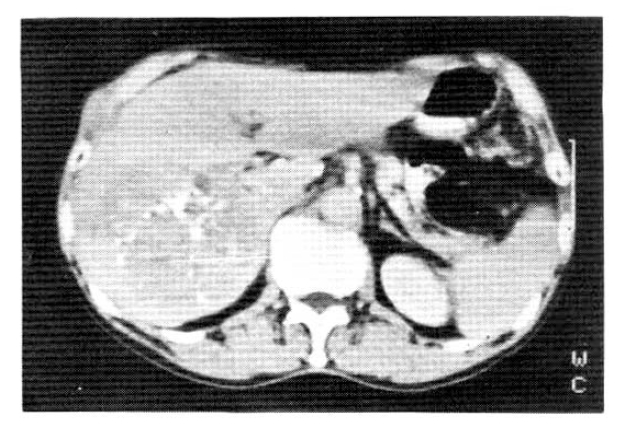

A 67-year-old male was admitted to Catholic University Medical College, Kangnam Hospital on October 18, 1987, for the evaluation of a right hepatic mass that was detected incidentally by ultrasonograhy. On admission, neither jaundice nor ascites were present. The liver was about 5 cm below the right subcostal margin. The serum hepatitis B viral surface antigen and antibody were both negative. The liver function tests revealed total protein (6–8 g/dl) 7.7 g/dl, albumin (3.5–5.0 g/dl) 4.1 g/dl, globulin (2.0–3.5 g/dl) 3.7 g/dl, aspartate aminotransferase (40 units) 72 units, alanine aminotransferase (40 units) 64 units, r-glutamyl transpeptidase (upto 80 mU/ml in adult male) 294 mU/ml, and alkaline phosphatase (upto 150 IU/L) 484 IU/L. An abdominal CT scan confirmed a large ovoid inhomogeneous hypodense mass involving the right posterior area of the liver, measuring about 9×9 × 8 cm. It was inhomogeneously enhanced with well demarcation (Fig. 1). On October 20, we did a peritoneoscopy that showed neither the cirrhotic nodules nor the abnormal protruding masses within the area of the visible hepatic surface. On Oct. 23, a percutaneous ultrasono-guided needle biopsy was done by a fine needle followed by transcatheter chemoembolization, a combination of transarterial infusion of Lipiodol and mitomycin-C 2 mg. On histopathologic examination, the tissue specimens taken by peritoneoscopic guided biopsy with a Menghini needle and ultrasono-guided aspiration biopsy showed chronic persistent hepatitis (Fig. 2a) and a well differentiated trabecular hepatocellular carcinoma (Fig. 2b) respectively. The patient was discharged on November 16, 1987, with a sense of well-being.

Fig. 1.

Abdominal CT scan showed an inhomogeneously enhanced hepatic tumor with well demarcation. (9 × 9 × 8 cm).